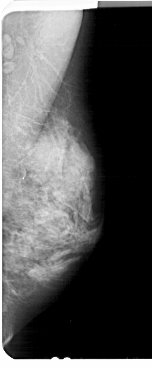

A_1926_1.LEFT_CC

LEFT_CC LINES 4966 PIXELS_PER_LINE 2296 BITS_PER_PIXEL 12 RESOLUTION 43.5 OVERLAY

FILE: A_1926_1.LEFT_CC.OVERLAY

TOTAL_ABNORMALITIES 1

ABNORMALITY 1

LESION_TYPE CALCIFICATION TYPE PLEOMORPHIC DISTRIBUTION CLUSTERED

ASSESSMENT 4

SUBTLETY 2

PATHOLOGY BENIGN

TOTAL_OUTLINES 1

BOUNDARY